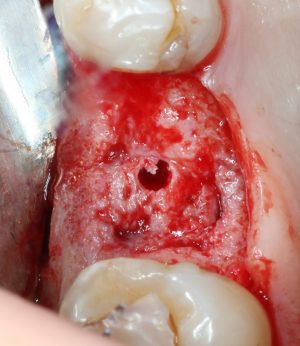

После этого можно еще раз (последний, кстати), проверить направление и ангуляцию оси будущего имплантата. Всё тем же вышеозначенным пином:

Если бы мы хотели поставить имплантат диаметром 4.5 мм, то далее мы перешли бы к кортикальной конической фрезе. Однако ж, я посчитал, имплантат диаметром 5.0 мм в данной клинической ситуации будет более надежным и органичным, поэтому мы продолжаем подготовку лунки. И следующая используемая фреза — 3.2/3.7 — то же самое. что и предыдущая, с направляющей 3.2 мм:

Кортикальная фреза погружается строго до отметки (см выше). В нашем клиническом случае (с синуслифтингом) это особенно важно, чтобы имплантат не улетел в субантральное пространство. Таким образом получаем лунку, полностью конгруэнтную будущему имплантату. Это очень-очень важно: